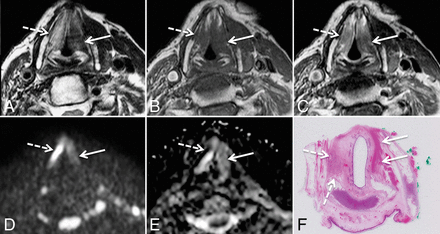

DWIMRI obtained 23 months after RTH for laryngeal squamous cell carcinoma and increasing hoarseness. Axial T2 (A), T1 (B), and contrast-enhanced T1 (C) show an oval lesion (arrows) in the left false cord and left paraglottic space with intermediate signal intensity on T2, low signal intensity on T1, and moderate contrast enhancement highly suspicious for rHNSCC. The b=1000 image (D) shows high signal intensity in the lesion. ADC map (E) reveals low signal intensity compatible with restricted diffusion (arrow), further suggesting recurrence (ADCmean = 0.798 × 10−3 mm2/s). Endoscopic biopsy confirmed rHNSCC. F, Histology (H&E, original magnification ×100) shows squamous cell carcinoma with areas of densely packed and loosely packed squamous cells of variable size with keratin pearls (asterisk).